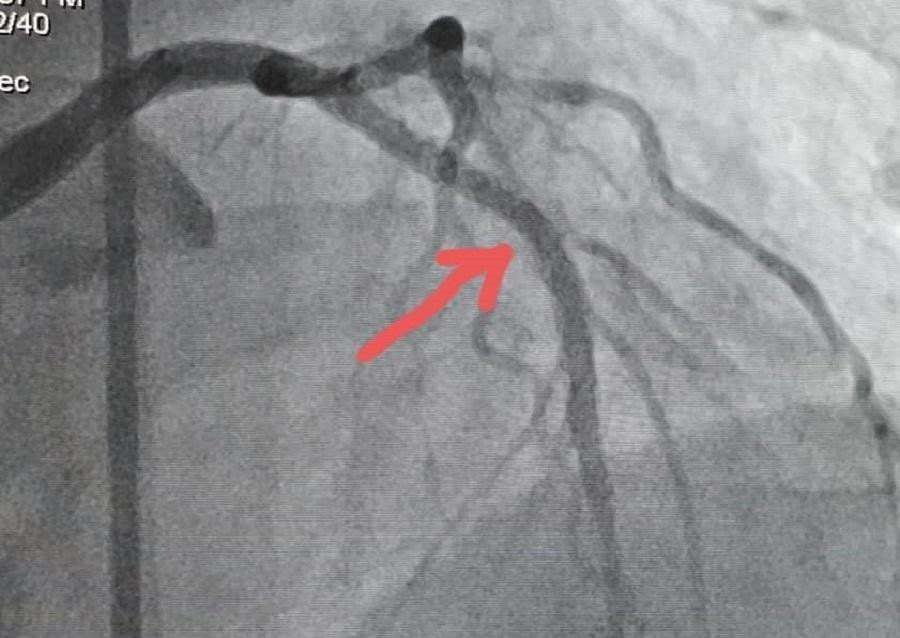

Sau 15 phút nỗ lực hồi sức, bệnh nhân có nhịp tim trở lại dưới sự hỗ trợ của máy thở, sử dụng thuốc nâng nhịp tim. Khi các chỉ số sinh hiệu tạm ổn định, ê kíp bác sĩ tiếp tiếp tục thông tim đặt stent thành công, khơi thông mạch vành bị tắc nghẽn. Sau 2 giờ khẩn trương trong phòng thông tim can thiệp, các bác sĩ đã giúp bệnh nhân vượt qua được cơn nguy cấp.

| Hình ảnh động mạch vành của bệnh nhân trước và sau khi được thông tim đặt stent |